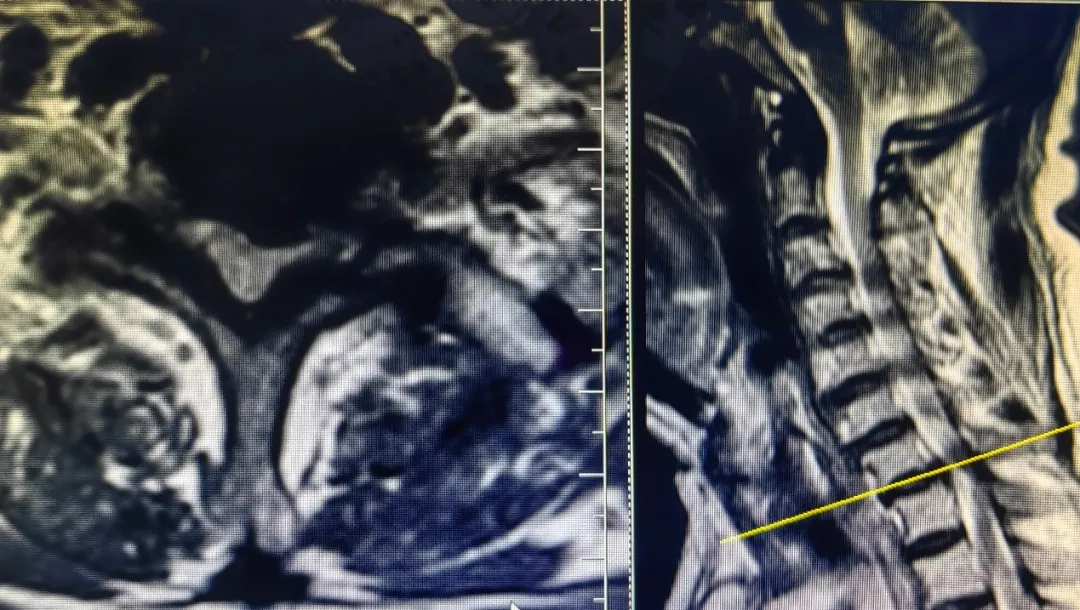

患者,男性,左上肢内侧疼痛剧烈,保守治疗无效,就诊于91直播 脊柱外科中心B区,诊断为神经根型颈椎病,C7/T1节段,左侧神经根管骨质增生严重,颈前路手术因胸骨阻挡难以实施,后路手术减压风险高、担心减压不彻底且创伤大。赵文奎博士了解患者病情后,用北医三院的诊疗理念,从影像学资料研判、诊断与鉴别诊断、治疗方案的制定等不同方面进行了详细分析,与91直播 脊柱外科中心B区医疗团队共同为患者制定了“精准化”手术方案——经皮内镜颈椎椎板切除神经根管减压术。

上图为术后复查CT

可见神经根管较术前变宽